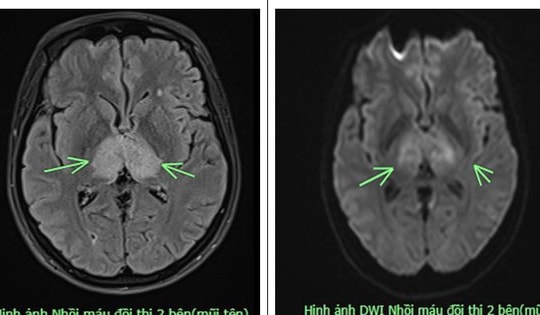

Chóng mặt, buồn nôn, người đàn ông ở Quảng Ninh phải nhập viện khẩn

Các bác sĩ cho biết, bệnh nhân có nguy cơ cao bị nhồi máu não gây liệt hoàn toàn thậm chí có thể gây tử vong nếu không được can thiệp kịp thời.